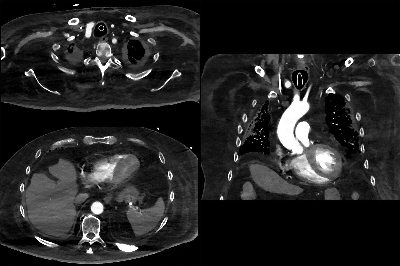

Investigaciones previas del laboratorio de Perlson habían demostrado que, en la ELA, una proteína llamada TDP-43 se agrupa en cantidades tóxicas en las uniones neuromusculares (el punto donde las neuronas se conectan con las fibras musculares).

En la ELA, se vuelve inestable y se acumula, dañando especialmente a las mitocondrias de las neuronas motoras.

- la acumulación de TDP-43 se redujo,

- el daño mitocondrial disminuyó, y

- las neuronas motoras dejaron de degenerarse y comenzaron a regenerarse.